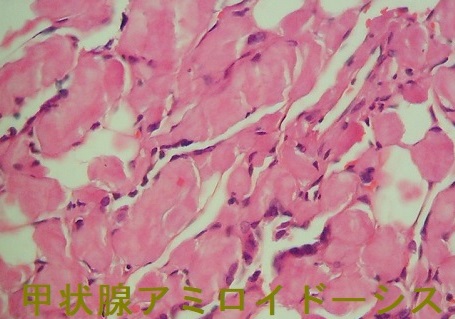

甲状腺アミロイドーシスの組織診

橋本病に合併した結節性甲状腺アミロイドーシスの病理組織標本では、

- アミロイド結節内の甲状腺濾胞構造は破壊され、異物反応や石灰化も存在する(第57回 日本甲状腺学会 P2-061 橋本病に合併した甲状腺amyloidosis の一例)

- アミロイド結節周囲の甲状腺組織には、リンパ球・形質細胞の炎症性細胞浸潤とリンパ濾胞形成を認めます。これらのリンパ球・形質細胞が、IgGのκ鎖を産生するのが原因では?と推察しますが、原因不明です。(第58回 日本甲状腺学会 P1-12-3 橋本病に合併した甲状腺限局免疫グロブリン軽鎖amyloidosisの一例)

- アミロイド沈着物は、細胞質内に小アミロイド滴を含む多数の組織球と多核巨細胞に囲まれる。しかし、血管壁にアミロイド沈着は無し。免疫組織化学検査により、アミロイドはアミロイドP成分、IgG、κ軽鎖が強陽性で、IgG、特にκ軽鎖(AL)が前駆体タンパク質と判明。[Acta Pathol Jpn. 1992 Mar;42(3):210-6.]。